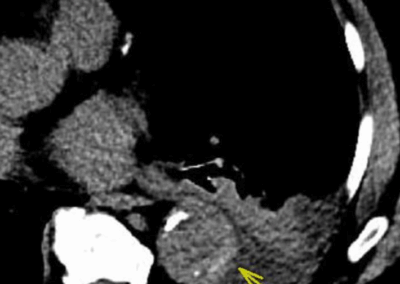

Pulmonary artery aneurysm (PAA) in a 63-year-old female with idiopathic pulmonary hypertension.

A. Surveillance CTA performed with Saline Jump protocol. Note the markedly enlarged left pulmonary artery (arrow).

B. Previous CTA with previous protocol. Note no significant change in PAA size (arrow) or diagnostic quality.